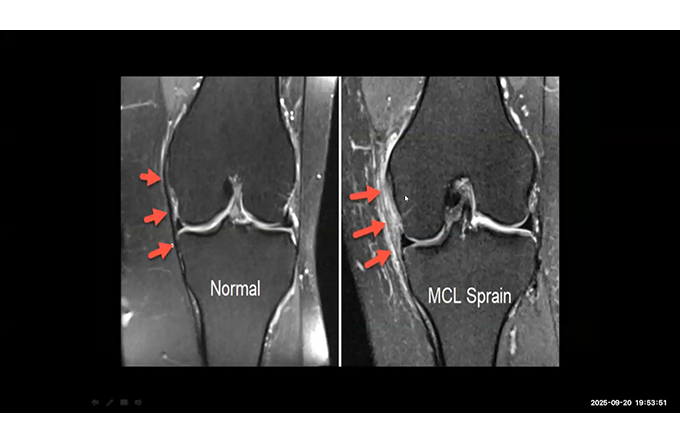

Only Cases - Breast Part-II